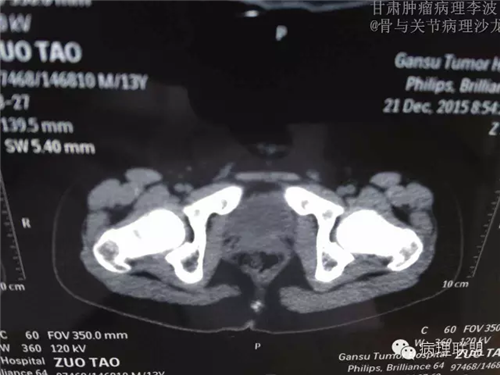

M/14 骶骨骨肉瘤-张惠箴讲解

病例由甘肃肿瘤病理 李波 提供,致谢。